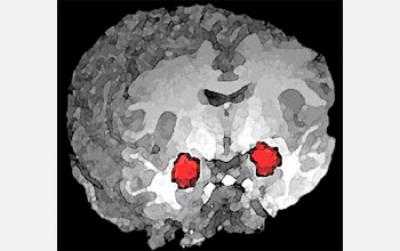

image: A new study supports the role of a brain region called the amygdala in processing anxiety. In this 3-D magnetic resonance imaging (MRI) rendering of a human brain, functional MRI (fMRI) activation of the amygdala is highlighted in red. view more

Credit: NIMH Clinical Brain Disorders Branch

The pathways are in a brain region called the amygdala. Prior research suggests the amygdala plays a role in anxiety, but earlier studies used widespread modifications of the amygdala, through drugs or physical disruption of the brain region, to study the way in which it affects anxiety. This new work, published in this week's Nature, uses a tool called optogenetics--developed by Deisseroth and recently named Method of the Year by Nature Methods--to specifically tease out which pathways contribute to anxiety.